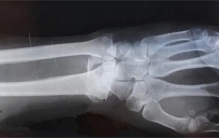

遭遇车祸没有骨折的男子 是不是超级英雄(超能力)

美国一男子的骨骼密度超高遭遇车祸都没有骨折。应该有不少人都梦想过自己什么时候能够拥有超能力。尤其是在看过一些超级英雄电影的时候,是想着自己拥有超能力的话该有多好,而在现实生活当中,有的人可能是因为自己 ...